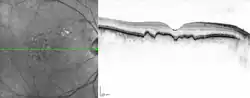

| Macular soft drusen in the right eye of a 70-year-old male. | |

Drusen, from the German word for node or geode (singular, "Druse"), are tiny yellow or white accumulations of extracellular material that build up between Bruch's membrane and the retinal pigment epithelium of the eye. The presence of a few small ("hard") drusen is normal with advancing age, and most people over 40 have some hard drusen.[1] However, the presence of larger and more numerous drusen in the macula is a common early sign of age-related macular degeneration (AMD).